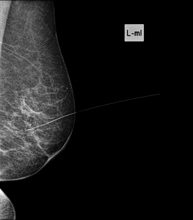

Pre-surgical harpoon marking

Small, non-palpable breast lesions requiring limited surgery, which need to be marked prior to the procedure by placing a harpoon in the area to be examined. The harpoon is a thin wire with an angled tip (harpoon) that remains fixed in the designated area of the breast. Under mammographic or ultrasound guidance, the radiologist inserts the harpoon into the lesion, where it remains fixed. This will enable the surgeon to locate the injury safely. The average duration of the procedure is 20 minutes and causes slight discomfort. It is usually performed a few hours before going into the operating theatre, although it can be done the day before.